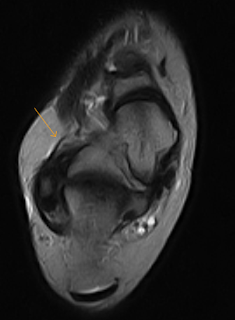

This is 24 year old soccer player with chronic ankle pain. Evidence of soft tissue hypertrophy and thickening/scarring in the anterolateral gutter of the ankle possibly indicating anterolateral impingement likely secondary to inversion injury. This appears separate from an intact anterior talofibular ligament.

Anterolateral impingement of the ankle is uncommon cause of chronic lateral ankle pain produced by entrapment of abnormal soft tissue in the anterolateral gutter of the ankle. Anterolateral impingement occurs subsequent to minor inversion injuries of the ankle. Repeated microtrauma results in hypertrophied synovial tissue and fibrosis in the anterolateral gutter of the ankle causing pain and mechanical impingement.